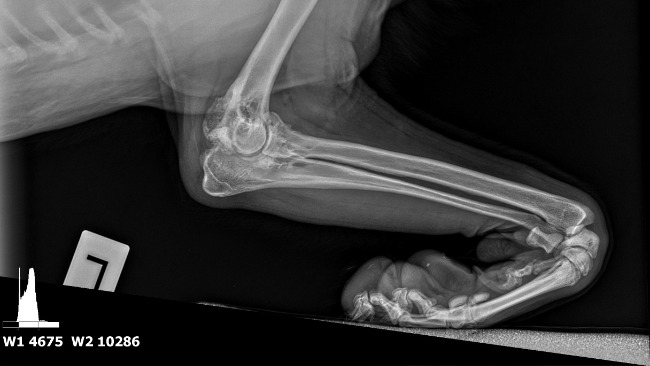

Nóżka Kokoszka, choć nadal obrzęknięta, dobrze się goi i nasz dzielny psiak stawia na niej swoje wielkie łapeczki.

Fot. Droga chłopaków do równowagi psychicznej. Wizyty w gabinecie lek.wet.

Małgorzata Płoskonka